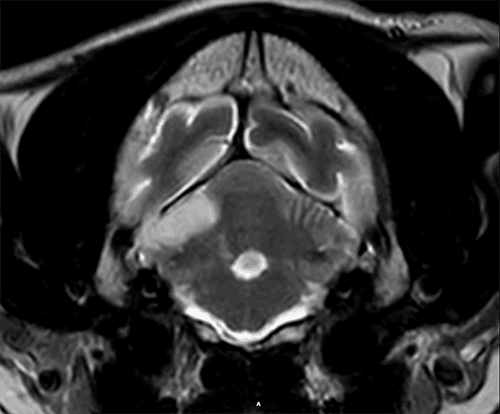

Kenji, a 14-year-old male Japanese Shiba Inu, presented to the neurology department at Eastcott following a hyperacute onset of inability to walk, severe left head tilt and left side rolling. He was neurolocalised in the central vestibular system and MRI documented changes consistent with an ischemic stroke affecting the right cerebellar hemisphere and interpositus nucleus. Kenji was hospitalized for supportive treatment during 5 days. A complete screening was realized to found the cause of the stroke, but all the results became unremarkable, showing that Kenji was healthy otherwise. He recovers completely after 2 weeks, and he is able to enjoy his life again.